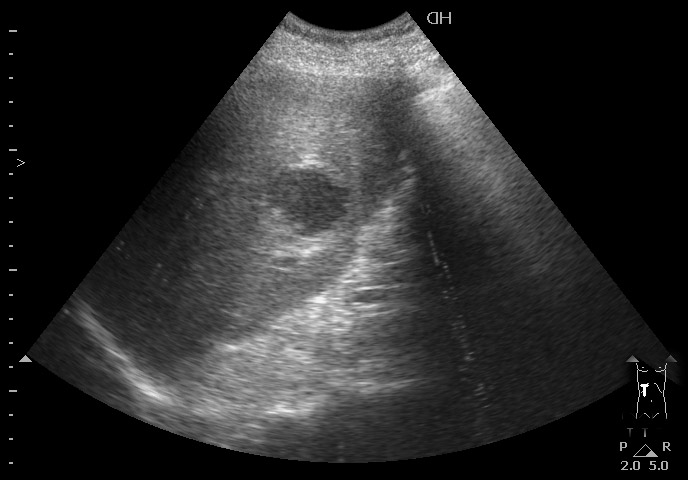

Типичная картина ##1-4:

Гипоэхогенное неоднородное округлое образование, окруженное эхогенным "демаркационным валом"

измененной паренхимы печени.